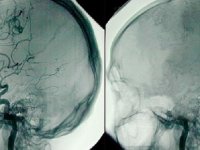

- DR.GÖKHAN İLHAN:BEYİN ÖLÜMÜ GERÇEKLEŞEN HASTANIN GERİ DÖNMESİ MÜMKÜN DEĞİLDİR''03 Aralık 2019 Salı 13:41